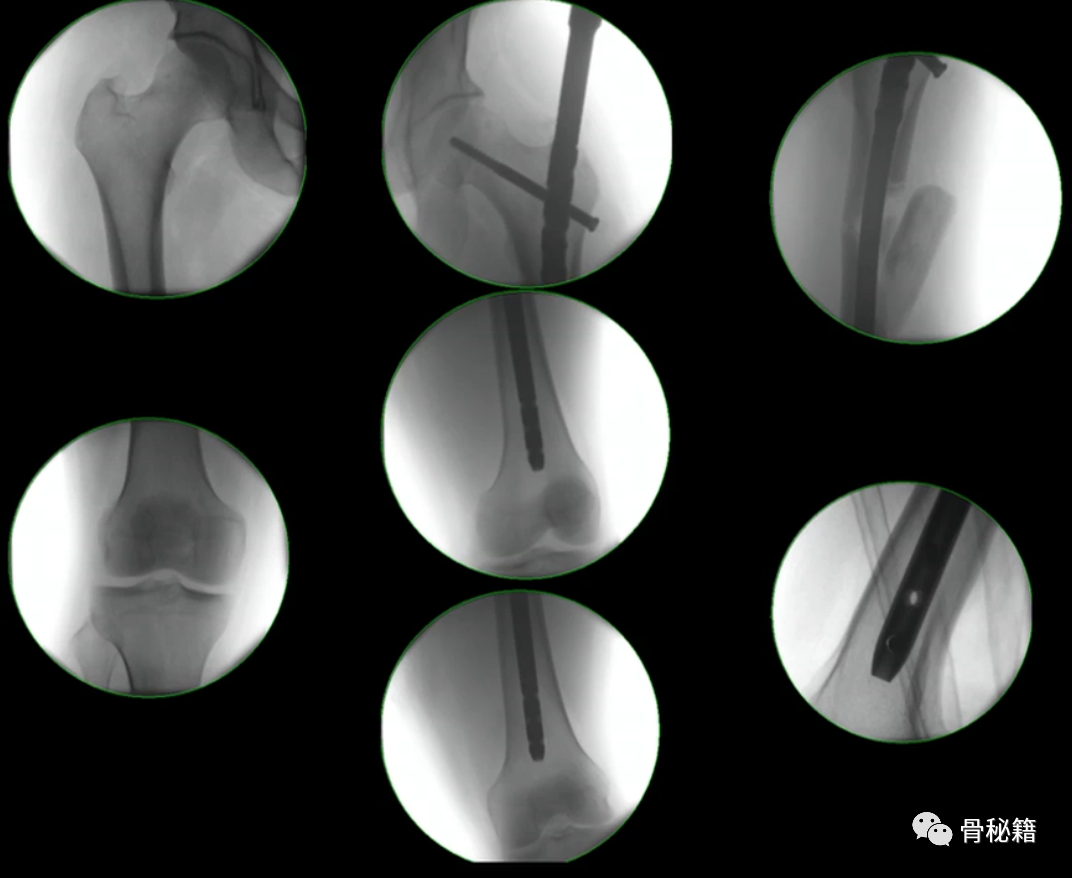

4、注意旋转。有的时候我们不太注意这个问题,有的时候中间比较粉碎,旋转容易忽略,一般来说是保持一个标准正位,近端是看小粗隆的形态,大约露出1/3-2/3,远端是看髌骨在不在两个股骨髁的中间

该例患者在复位置钉后发现远端髌骨不在股骨髁的中心,后进行旋转调整。

5、钉子的深度。逆行髓内钉的最佳深度是布鲁门萨线的顶点位置,正位居中

近端一般是小粗隆水平以上

6最后提一点锁钉的小技巧,不要造成主任打主钉5分钟,我们锁钉2小时。我们透视的时候,要把锁定空透成两个圆形,但是在操作中往往是椭圆形,这个时候根据椭圆形的长轴来方向来移动C臂,就可以透一个好的圆形了,在此情况下完成锁钉就相对容易些。